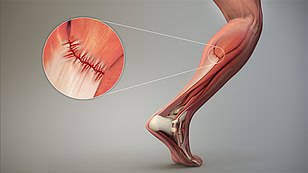

بهترین دکتر کشیدگی عضلات در کرج + لیست 10 تایی